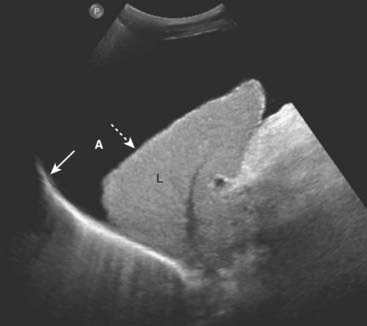

Ascites

imageAscites is the abnormal accumulation of fluid in the peritoneal cavity. In the recumbent position, ascitic fluid flows up the right paracolic gutter to the right subphrenic space so ascites is generally easier to detect by ultrasound in the right upper quadrant between the liver and the diaphragm.

image Ascitic fluid that is a transudate is primarily sonolucent. Fluid collections that are exudates or contain hemorrhage or pus may contain echoes (Fig. 19-24).

image

Figure 19-24 Ascites, sagittal US.

Ascitic fluid flows up the right paracolic gutter to the right subphrenic space so ascites (A) is generally easier to detect by ultrasound in the right upper quadrant between the liver (L) and the diaphragm (solid white arrow). The liver is contracted and has a nodular margin (dotted white arrow), both features of cirrhosis. If the fluid is a transudate, as in this case of ascites due to cirrhosis, the fluid will be anechoic. Exudates will produce internal echoes.